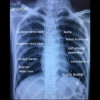

Gambar 1. Hasil Rontgen Thorax Posisi PA. Sumber: Shutterstock, 2023.